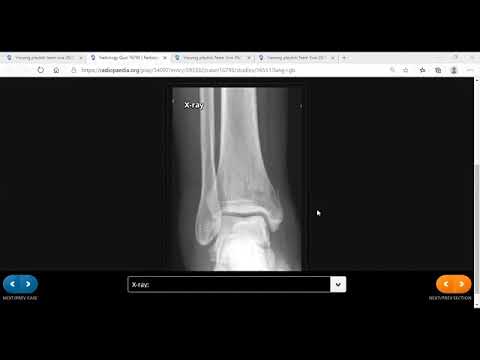

TEAM FRCR 2B Viva Practice Session (MSK Module). 1st Jan, 2022

TEAM FRCR 2B Viva Practice Session (MSK module). 28th Nov, 2020.

TEAM FRCR 2B Viva Practice Session (MSK, GU & Breast Modules Revision). 12th December, 2020.